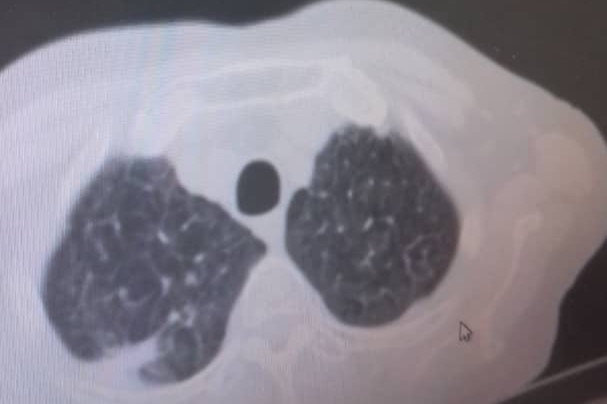

En septiembre de 2019 fue diagnosticada con cáncer de pulmón con una Lesión Ocupante de Espacio (LOE) de 2,5 cm y otra lesión en el Mediastino de 5,4 x 4,7 cm.

A través de varios familiares hemos logrado conseguir dinero para realizarle 36 ciclos de radioterapia y 6 de quimioterapia, además del tratamiento y todos los medicamentos requeridos hasta ahora, logrando una reducción importante del tamaño del tumor en pulmón en 40 %. Gracias a Dios la lesión en el mediastino se redujo también en un 80%.

In September 2019, she was diagnosed with lung cancer with a Space Occupying Injury (LOE) of 2.5 cm and another lesion in the Mediastinum of 5.4 x 4.7 cm.

Through several family members we have managed to raise money to perform 36 cycles of radiotherapy and 6 of chemotherapy, in addition to the treatment and all the medications required so far, achieving a significant reduction in the size of the tumor in the lung by 40%. Thank God the injury to the mediastinum was also reduced by 80%.